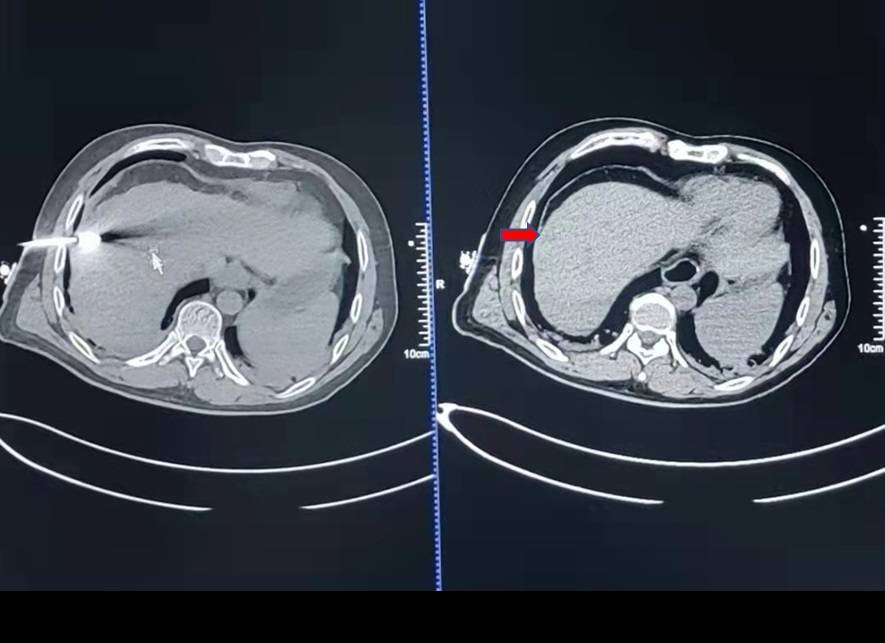

CT进行3D重建,进上图:IQQA术前eO时制导路径,将消融治疗针精确送入目标病灶位置,成功实施肝脏转移灶的全范围微波消融。手术顺利,患者无明显不适,术后复查CT,微波消融范围理想,无术后并发症。

消融治疗针精确送入目标病灶位置